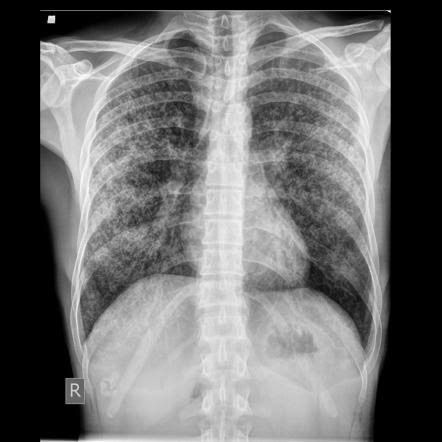

Miliary TB is a form of TB that results from the hematogenous and lymphogenous dissemination of the disease. The patient with miliary TB presents with extra-pulmonary manifestations like enlarged lymph nodes, hepatosplenomegaly, pancreatitis, multiple organ dysfunction and pneumothorax. The chest radiograph in cases of miliary TB will show distinctive tiny opacities called millet seeds spread all over the lung fields. Picture credit: https://radiopaedia.org/articles/miliary-tuberculosis